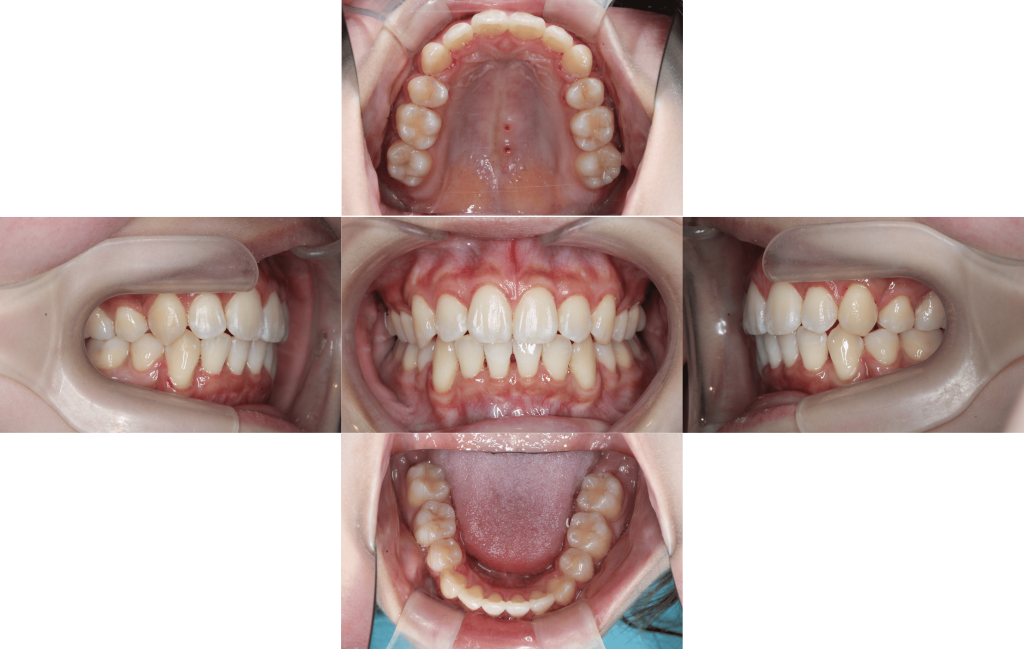

After

約1年10か月後